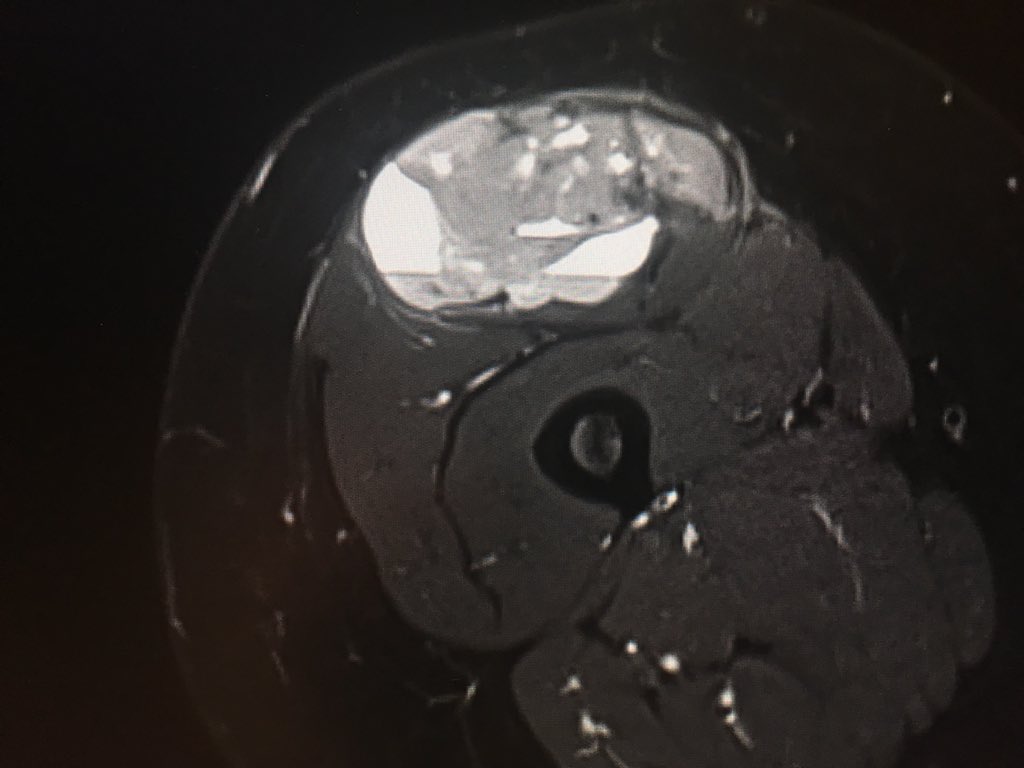

Going a little further back in the archive this week. 'Symptomatic ganglion cyst' at the knee. To read the case history, follow the link. https://www.jospt.org/doi/full/10.2519/jospt.2014.0412 …

#MSKMonday#MSKImaging#MRI#physio#yourJOSPTpic.twitter.com/VNw7p2Xr3X